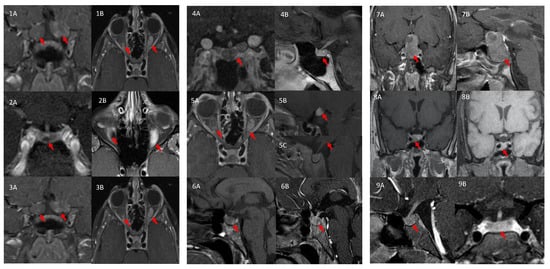

3.1.1. Patient 1

3.1.2. Patient 2

3.1.3. Patient 3

3.1.4. Patient 4

3.1.5. Patient 5

3.1.6. Patient 6

3.1.7. Patient 7

3.1.8. Patient 8

3.1.9. Patient 9

| ID | Pituitary MRI | Pathology | Family History of NF1 |

|---|---|---|---|

| 1 | No tumor | N/A | Positive |

| 2 | Microadenoma (~5 mm) | Pituitary tumor stained negative for GH, patchy positive for GPR101, positive for NF1 | Positive |

| 3 | No tumor | N/A | Negative |

| 4 | No tumor | OPG stained positive for GPR101 (cytoplasmic signal), negative for GHRH, GH, and somatostatin and weakly positive for GH | Positive |

| 5 | No tumor | GIST stained patchy positive for GPR101 and small nuclear staining in pNET | Positive |

| 6 | No tumor; hypothalamic infiltration | N/A | Negative |

| 7 | Voluminous pituitary gland with Rathke’s cyst | N/A | Negative |

| 8 | Macroadenoma (~1 × 0.5 cm) | Pituitary tumor stained positive for GH, PRL and NF1, and patchy positive for GPR101 | Negative |

| 9 | Macroadenoma (~1.4 cm) | N/A | Negative |

| 10 | No tumor; Right inferior hypothalamic enhancement | N/A | Negative |